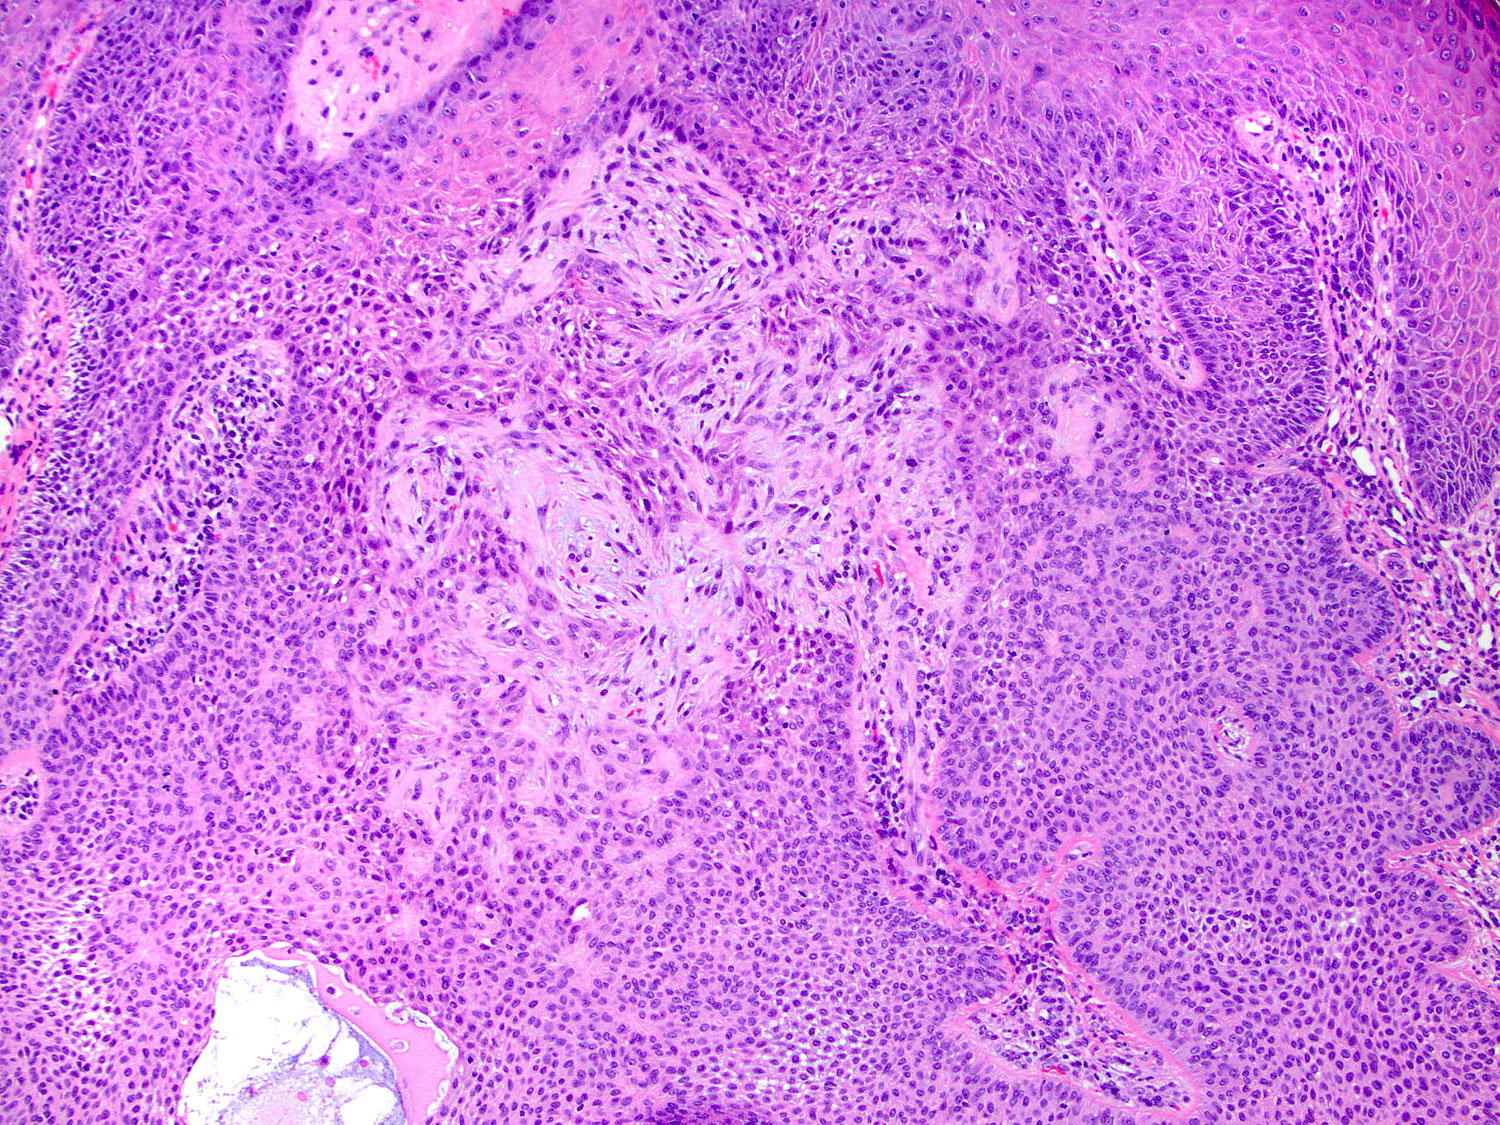

H&E staining (10x objective)